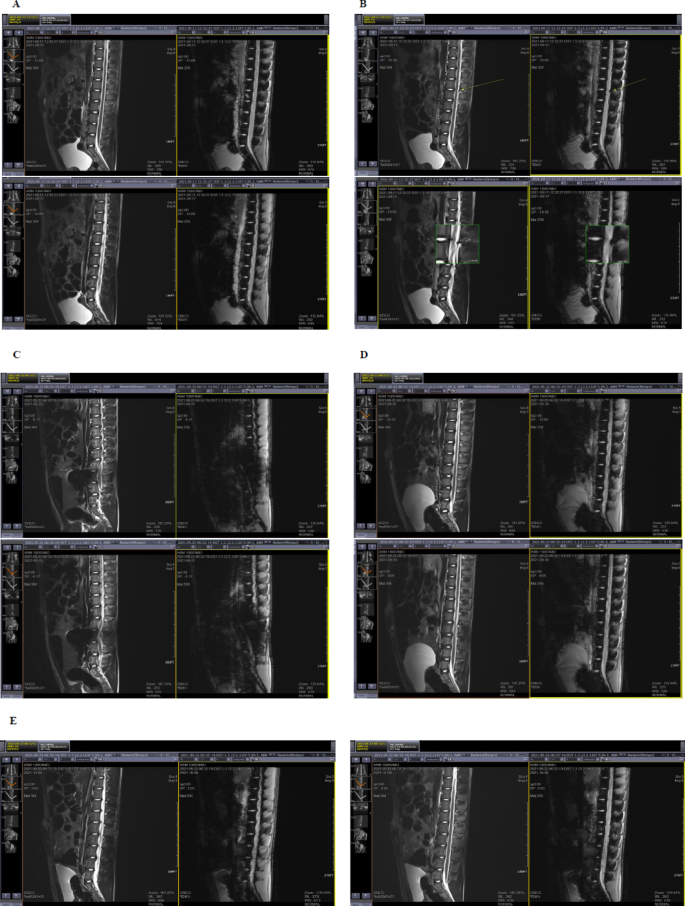

The analysis of MRI images after MSC/NTs administration was compared with images obtained before the start of the administration procedure. In control animals, no changes were observed in any MRI sequences (T2-TSE-COR, T2-TSE-SAG, T2-FL2D-SAG-HEMO, T2-TSE-TRA, T2-SPC-SAG-ISO-1.0MM) after placebo administration compared to pre-surgery images (Fig. 8A). In images acquired before the start of cell/NaCl administration, no artifacts were detected in the spinal canal.

MRI images from animals that received MSC/NTs in the operating room and were subsequently transported to the MRI laboratory also showed no artifacts (Fig. 8B–E), likely due to dilution and redistribution of cells in the cerebrospinal fluid during transport.

In contrast, images acquired during intrathecal cell administration under MRI guidance revealed localized hypointense signals on T2-weighted sequences (T2-TSE-COR, T2-TSE-SAG, T2-TSE-TRA), characteristic of iron-labeled cells (Fig. 9A–D). These signals were observed approximately 10 cm above the drain insertion site, consistent with the recorded drain length, confirming the location of administered cells within the spinal canal.

No MRI changes were observed in animals receiving cells postoperatively after transport, nor in control animals after placebo administration (Fig. 8A–E). MRI images acquired one week after the last surgical procedures showed no alterations in the spinal canal in any study group. Throughout the experiment, animal caretakers did not report any deviations from normal health, supporting the safety of the intrathecal administration method.

MRI visualization of intrathecal administration of mesenchymal stem/stromal cells (MSCs) and neurotrophin-releasing nanoparticles in pigs. Representative sagittal T2-weighted MRI images obtained at different stages of the experiment: (A) baseline scan before any intervention, showing normal spinal canal appearance without artefacts; (B) immediately after the first intrathecal administration of MSCs/NaCl, with arrows indicating the injection site and cerebrospinal fluid space; (C) one week after the second administration, showing no pathological signal changes; (D) after neurotrophin (NTs) administration, showing mild hypointense signal in the spinal canal corresponding to iron-labelled MSCs suspended in cerebrospinal fluid; (E) one week after the final procedure, showing complete normalization and absence of hypointense artefacts.